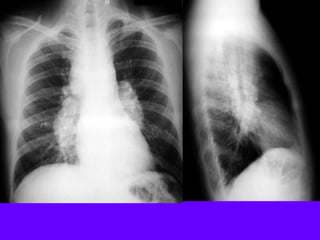

Upper lobe Bulla

Lower lobe Bulla

A: Xray shows bilateral bulla.

B: CT shows bilateral bulla.

C: CT after bullectomy.